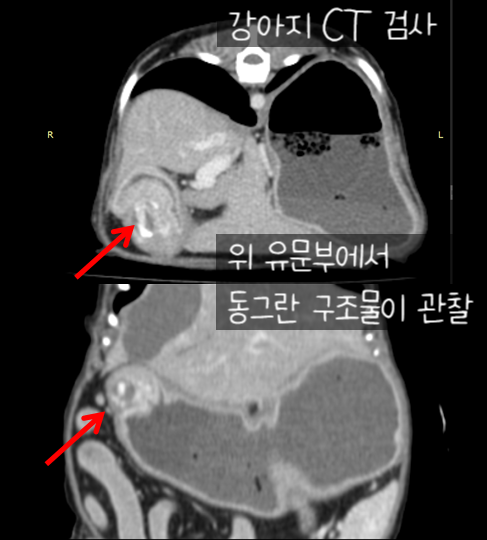

개의 위암 CT 검사

상유문부의 위치에서 경계가 불분명한 둥근 구조물이 관찰되었습니다.(크기 : 0.98cm*0.76cm*0.97cm)

폐 겹엽, 양측 후엽, 우측 중엽에서 군데군데 폐결절이 관찰되고 있습니다.